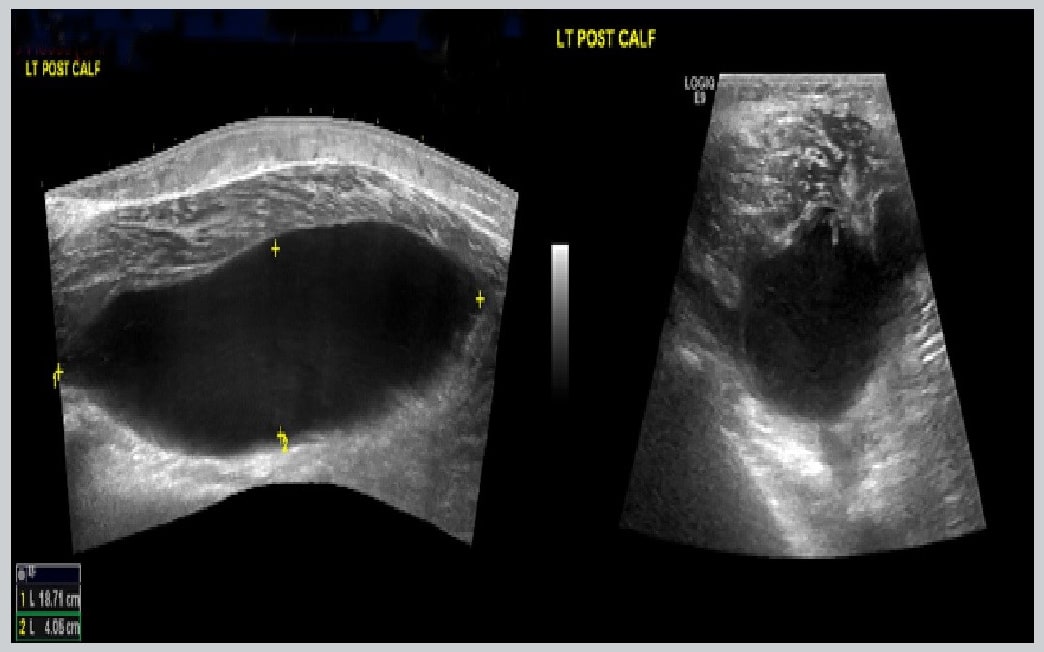

En 32-år gammel ble presentert til akuttmottak med en historie av to dager med akutt svelling og smerte i venstre legg. Pasienten hadde en historie med hepatitt C, intravenøs bruk av legemidler med tidligere inntak på grunn av gjentatte bløtvevsabsess på legemiddelinnsprøytningssteder. Pasienten nektet noe traume i beinet og tok ikke regelmessig medisinering. Under undersøkelsen ble det merket hevelse og ømhet i venstre kalv. Hadde en temperatur på 37,7 ° C, en hjertefrekvens på 110 slag / min, arterietrykk 110/707 mm Hg, og en lufthastighet på 18 åndedrag / min. En trepunkts kompresjons-ultralyd (POCUS) ble utført på beinet som viste ingen tegn på DVT; Imidlertid ble en stor cystisk struktur identifisert på baksiden av kalven (Figur 1). En ultralyd av kneet viste også et væskefylt område som foreslo et tilknyttet kneevirkning. Et knesøkt avslørte et antall hvite blodlegemer på 135 000 celler / μl, med 95% nøytrofiler (Figur 2). Pasienten ble tatt opp til ortopedikk med en mistenkt diagnose av septisk kne og en infisert og ødelagt Baker’s cyste. Resultatene av blodprøver ved opptakstidspunkt er vist i tilleggsmateriale (tabell S1 online). En Doppler-ultralyd av en pasient i pasienten utelukket DVT. Muskel-og ultralyd av venstre ben bekreftet resultatene av et ekstremt stort eller kompleks Baker infiserte med hemoragisk cyste. Pasienten ble først behandlet med intravenøs flukloxacillin. En kultur av knesøyling avslørte stafylokokker aureus. Pasienten ble planlagt for kirurgisk behandling, men han ble selv utladet fra sykehuset. Pasienten kom tilbake til sykehuset ubehag en måned senere, pirexial og klaget over smerter i høyre sternoclavicular området. Computertomografi (CT) i brystet viste akutt septisk artritt i riktig sternoclavicular felles med flaten slim og en liten flate ring øker foregående opphopning høyre halvdel kravebenet og, i større grad, mest sannsynlig forekomstene er sekundære til Staphylococcus aureus. Hevelse i kneet hadde forbedret men forble vedvarende symptomer, men pasienten nektet noen invasiv behandling og akseptert en intravenøs vancomycin behandling.

Dette tilfelle reflekterer nytten av Pocus i nødsituasjoner for å vurdere pasienter med muskel- og tilstander, i dette tilfellet kalv akutt smerte og hevelse, som er en vanlig presentasjon i beredskapsrommet. Ved den første presentasjonen ble DVT mistenkt. En ultralyd tre punkter viste femorale vener og komprimerbar popliteal uten åpenbare tegn på DVT, men en avaskulær bilde ble vist i popliteal grop 24 cm, cyste kommunisert med semimembranosa og mediale gastrocnémica bursa hode, også viste et utslipp i kneet. Saken ble behandlet med utstyr ortopedi og formell ultralyd bekreftet funnene og sprukket Baker infisert cyste som ble støttet ved forhøyede inflammatoriske markører og ble straks satt i gang intravenøs antibiotika mistenkt spurt. I de siste 10 årene har beredskapslærere forbedret kapasiteten til muskuloskeletale ultralyd (MSK). POCUS kan identifisere inflammerte eller flytende strukturer. Pokus endret behandling i 65% av pasientene med leddsmerter, hevelser og erytem og redusert felles aspirasjon planlagt 72,2 til 37% [8]. Huden, myke vev og de fleste deler av MSK-systemet er relativt overfladiske anatomiske strukturer og er ideelle mål for ultralyd. Ved hjelp av MSK POCUS kan beredskapsleger tilby bedre omsorg til pasienter med MSK-symptomer i HUS.